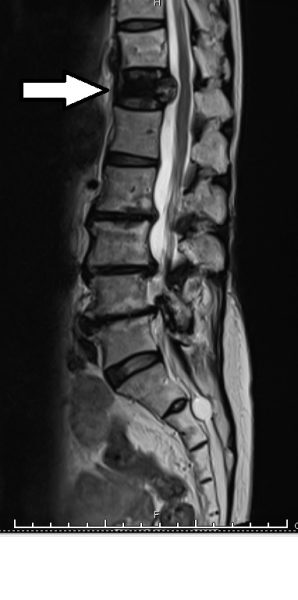

娟姐吃过止痛药后,疼痛稍微舒缓,但背还是无法挺直,外甥女见状,带她到诊所照了X光,才发现第12节胸椎塌陷了,引致剧痛。

在医生的劝告下,娟姐连夜住进医院,做了磁力共振扫描,“医生说骨头塌了,好在没有压到主要神经线,不然就要坐轮椅了。”说完,又絮絮叨叨地怨一身老骨头没有用,只不过是咳两声,竟然倾塌了。

扫描报告正常,意味可以排除病理性骨折的因素,并确定娟姐是因为年纪大骨质疏松,加上突然激烈咳嗽,造成胸椎塌陷。

排除了病理性骨折的因素(箭頭處)。.jpg)